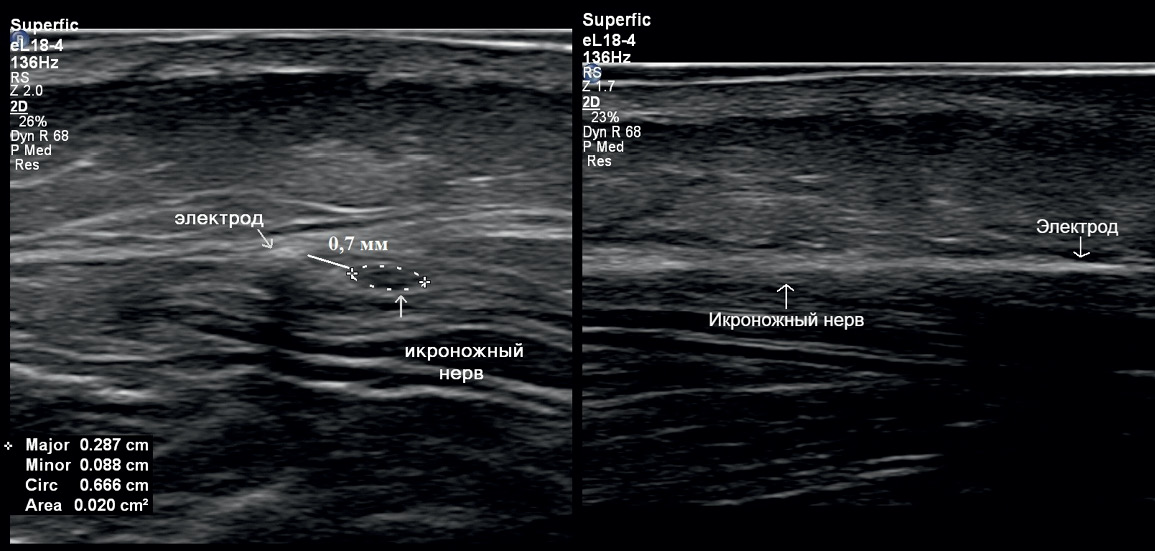

In 2023, the patient presented to the N.N. Burdenko National Medical Research Center of Neurosurgery, where she underwent a sural nerve block. Complete regression of the pain syndrome was observed during the local anesthetic effect, with complete recurrence of pain occurring on days 2–3 post-block. Consequently, a decision was made to implant an electrode for chronic electrical stimulation of the n. suralis under ultrasound guidance. A 3 cm linear incision was made on the posterolateral surface of the calf, through which the n. suralis trunk was identified under ultrasound guidance. Using a Tuohy epidural needle (provided with the electrode kit), the electrode was implanted parallel to the n. suralis course and secured at the incision site with a thick non-absorbable silk suture (5 metric) (Figs. 2, 3).

Fig. 3. Ultrasound image of the implanted electrode.

Left: transverse scan. The electrode runs along the trunk of the sural nerve (n. suralis) at a distance of less than 1 mm from it. Right: longitudinal scan. Aligning the electrode and n. suralis in the same plane is extremely challenging due to their spatial relationship, but the electrode shadow and epineurium of n. suralis can be visualized.